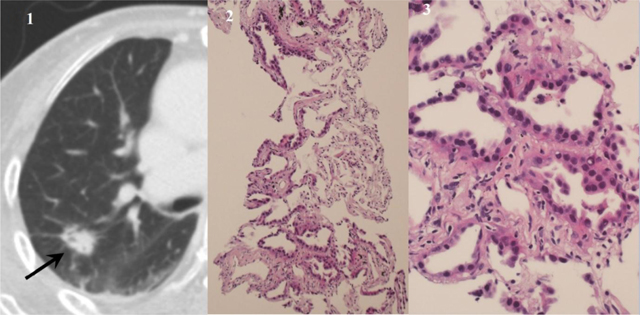

Figure 3

An adenocarcinoma with lepidic pattern diagnosed using samples from core needle biopsy. Diagnosis of fine needle aspiration was highly suspicious for adenocarcinoma. (1) CT image shows a nodule with inner bubble-like lucency in the right upper lobe (arrow). (2) Photomicrograph of a core biopsy (hematoxylin-eosin, original magnification × 100) shows lepidic growth along the alveolar interstitium with preserved alveolar architecture. (3) Magnified photomicrograph (hematoxylin-eosin, original magnification × 400) shows characteristic nonmucinous lepidic adenocarcinoma.